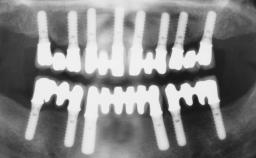

Immediate Loading of Six Implants in the Maxilla and Final Restoration with a Full-Arch CAD/CAM Zirconia FDP

# of Implants 6

Type of Implants One-Piece

Bone Augmentation Horizontal|Simultaneous

Abutment Type CAD/CAM

Prosthesis Type FDP